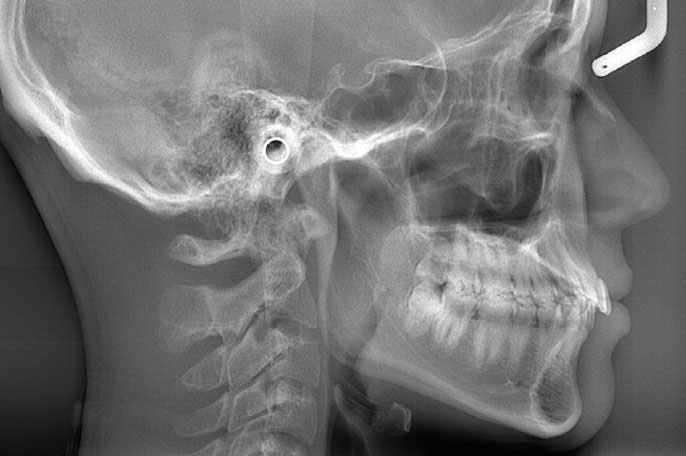

顔全体のバランスを考えた矯正

横顔や正面からお顔の骨格をレントゲン撮影し、顎の形や大きさ、ズレなどを頭部全体を通して調べ、バランスのよい矯正計画を立ててまいります。

<精密検査>

診療区分:自由診療

お口やお顔の写真、レントゲン、歯型の模型をとります。

費用:全顎33,000円(税込)、部分矯正22,000円(税込)